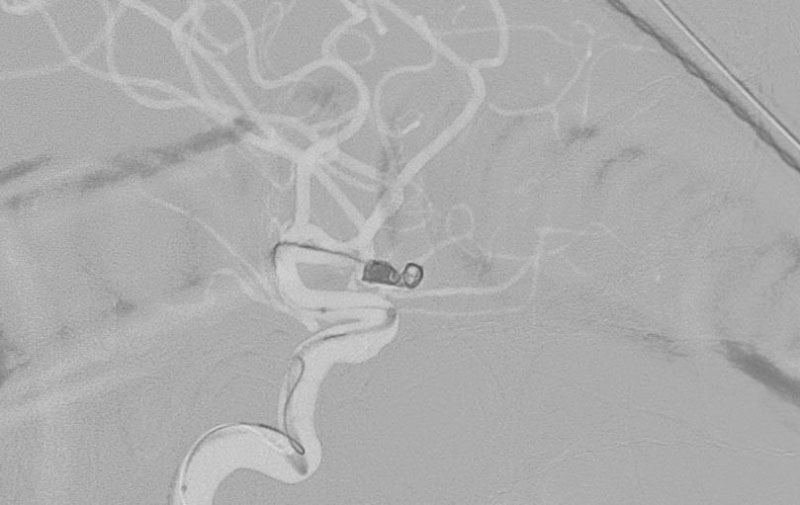

No.1596 手術中